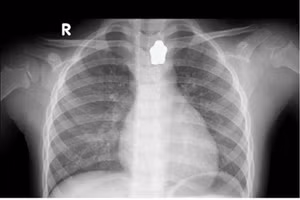

GD&TĐ - Ngày 16/4, Bệnh viện TP Thủ Đức (TPHCM) cho biết vừa tiếp nhận bệnh nhi N.N.N.Y (5 tuổi) nuốt phải nam châm hình ngôi sao trong lúc ăn cơm.